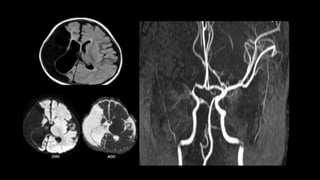

MULTIPLE EMBOLIC INFARCTS

cardiac emboli

GM-WM interface

•MR- multifocal peripheral T2/FLAIR hyperintensities

Differential diagnosis

 Hypotensive cerebral infarction – involve deep

internal watershed zones

 Parenchymal mets – do not restrict on DWI

• #165 Simultaneous small acute infarcts in multiple different vascular distribution…………..most commonly emboli is cardiac in origin Clinically silent , they convey risk of subsequent stroke

• #166 Diffusion wi shows multiple foci od hyperintensities in both the cerebral hemisphere and in multiple vascular territories..cortical , subcortical and deep regions are affected. Restriction is confirmed on ADC maps , indicating this represents acute infarcts. The distribution raises concern for central embolic source such as cardiac source.